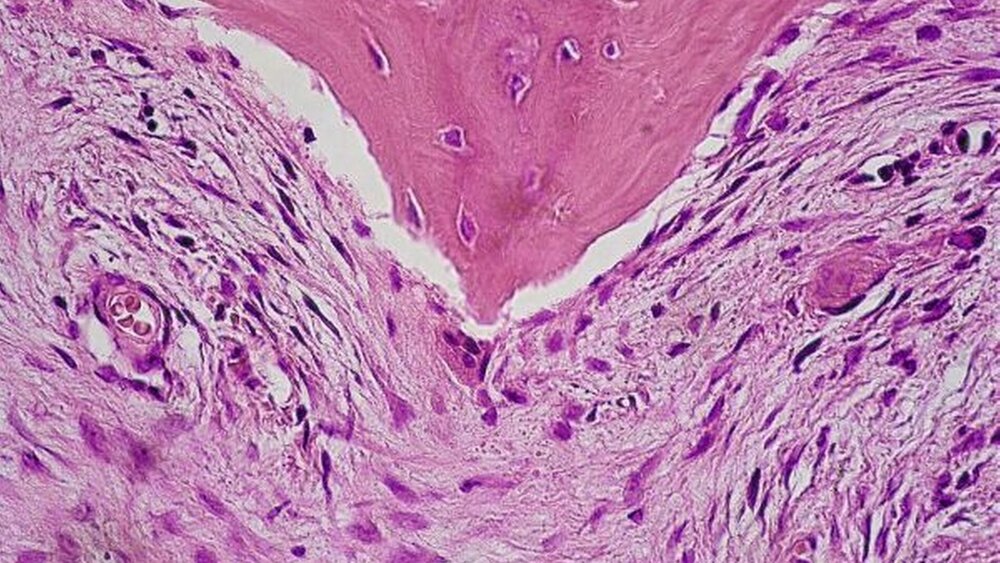

Mit der Verdachtsdiagnose einer fibrösen Dysplasie wurde der Patient im Sinne einer modellierenden Osteotomie der Mandibula operiert (Abbildung 4). Intraoperativ stellte sich der Unterkiefer zystisch durchsetzt und sehr gut durchblutet dar. Die postoperative digitale Volumentomographie zeigt noch immer die wolkige Knochenauftreibung der Mandibula bis in den aufsteigenden Ast sowie unscharf begrenzte Osteolysen (Abbildungen 5 und 6). Die histopathologische Aufbereitung erbrachte kortikospongiöses Knochengewebe mit irregulären Knochenbälkchen mit einem zelldichten spindel- artigen Proliferat mit partiell akzentuiert eingelagertem Knochengewebe – vereinbar mit der klinischen Verdachtsdiagnose einer fibrösen Dysplasie (Abbildung 7).

In Abhängigkeit des Gehalts an ossärem beziehungsweise fibrösem Gewebe zeigt sich radiologisch eine mehr oder weniger stark begrenzte bimssteinartige, milchglasartige Opazitätszunahme respektive zystoide Veränderung mit vergröberter Trabekelstruktur und Kortikalisausdünnung. Der Markraum ist hierbei makroskopisch durch grau-weißes

Bindegewebe ersetzt. Im histologischen Präparat findet sich ein trabekelförmiger Geflechtknochen, dem im Gegensatz zum ossifizierenden Knochenfibrom keine Osteoklasten oder Osteoblasten an-gelagert sind.